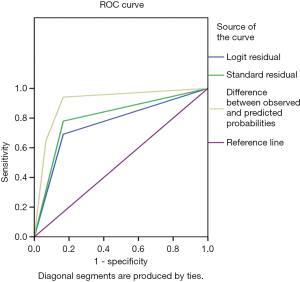

The G-test was used in the logistic regression with a G-value of 11.028, and a P value of 0.004. Using this logistic regression model, patient prognosis was predicted by P values calculated in logistic regression, and the predictive accuracy was 76.2%. The area under the receiver operating characteristic (ROC) curve (AUC) for pleural thickening was 0.762 (95% CI: 0.660–0.864, P=0.000), the sensitivity was 69.1%, and the specificity was 83.3%. The AUC for transparency was 0.806 (95% CI: 0.710–0.903, P=0.000), the sensitivity was 77.9%, and the specificity was 83.3%. The AUC for echo was 0.910 (95% CI: 0.838–0.981, P=0.000), the sensitivity was 94.1%, and the specificity was 83.3% (Figure 4).